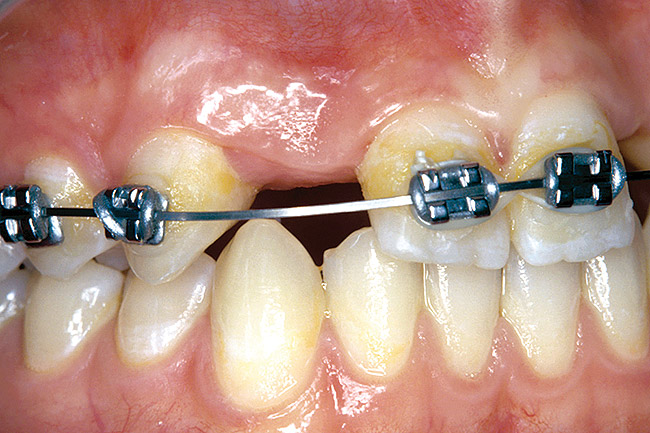

Periapical radiographs were taken to help determine the mesial-distal inclinations of the adjacent tooth roots (Figure 1). The radiographs revealed a serious issue, convergent roots for the right canine and right central, which eliminated that area as a potential implant-receptor site. The space between the left central and canine teeth was minimal, although the roots were relatively parallel. Clinical examination (manual palpation of the root eminences superiorly to the vestibule on the right side) confirmed the root convergence (Figure 2). The flat, wide zone of the keratinized tissue and lack of interdental papilla was evident for the missing right lateral incisor. There was a marked difference in clinical appearance for the left lateral, which could impact the eventual plan of treatment (Figure 3). Other significant clinical findings included bilateral facial bone concavities, which existed as a result of the congenitally missing tooth roots. As a diagnostic cue to the underlying bone topography, it is important to follow the demarcation between attached and unattached gingival tissue, and note the crestal width of the available keratinized tissue (Figure 4).

Figure 1  PRE-TREATMENT DIAGNOSTICS Pretreatment radiographs revealed convergent roots for the right canine and right central.

Figure 1

Figure 2  DIAGNOSTIC INFORMATION Root convergence, buccal view.

Figure 2

Figure 3  DIAGNOSTIC INFORMATION A difference in clinical appearance of the left lateral, buccal view.

Figure 3

Figure 4  DIAGNOSTIC INFORMATION Significant crestal width of keratinized tissue, buccal view.

Figure 4